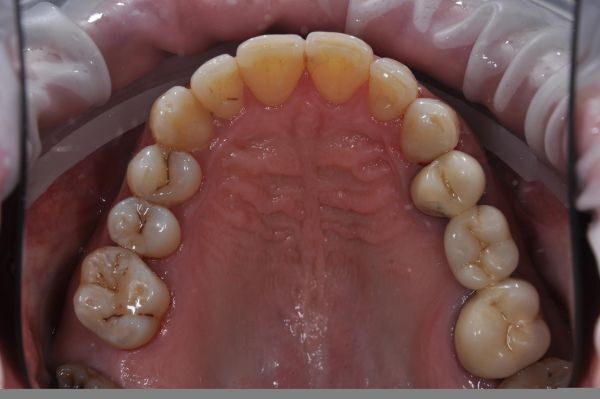

Композитная реставрация зубов: фото до и после

Одним из способов восстановления эстетики зубного ряда является композитная реставрация зубов. Ее проводят при необходимости устранения врожденных или приобретенных косметических дефектов, когда нужно исправить форму и цвет зубов, выровнять зубной ряд. И в большинстве случаев такая реставрация требует всего лишь одного посещения врача.